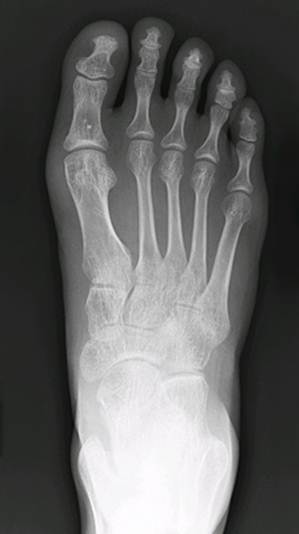

Notice how the toe box is tapered as if the shoe needs to be aerodynamic. This is purely aesthetic. Shoes should be shaped according to feet. In modern society, however, feet are shaped according to shoes:

On the left is the standard foot for a person who grew up wearing shoes. Notice how the bones are crooked instead of straight. On the right is a Photoshopped, hypothetical natural foot. The toes fan out.